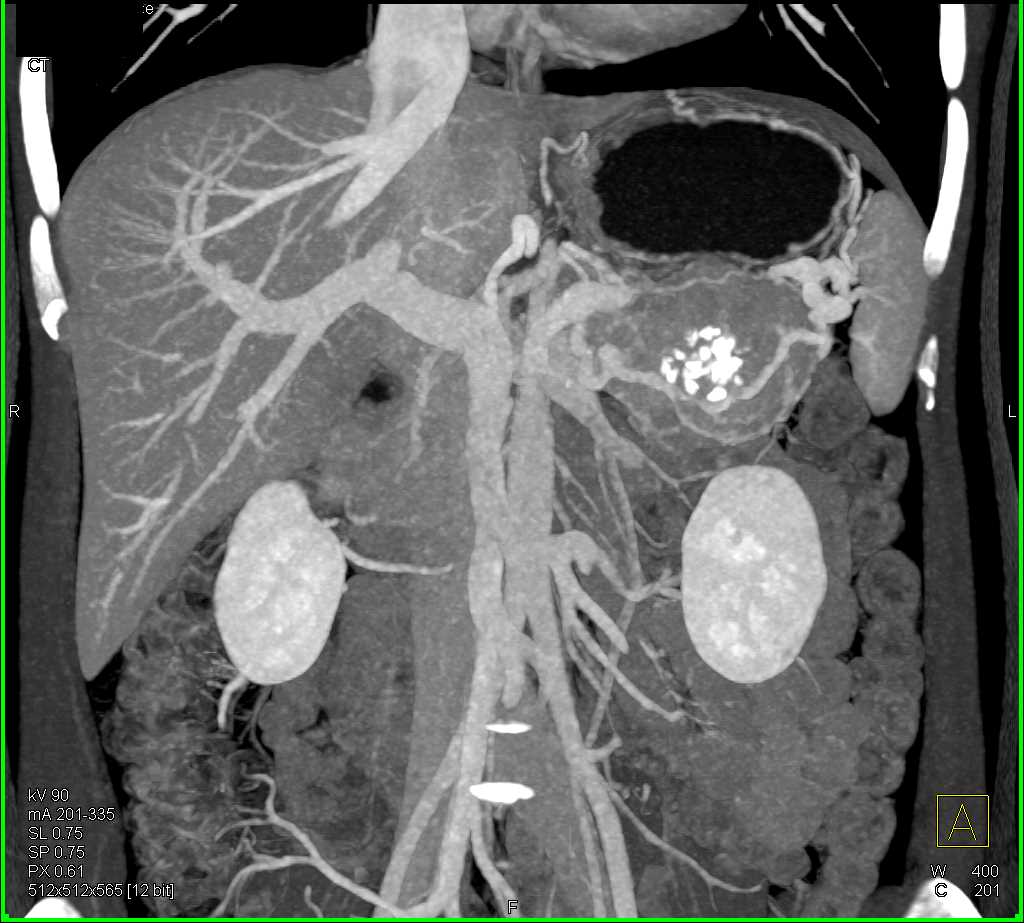

PNET Tail of the Pancreas